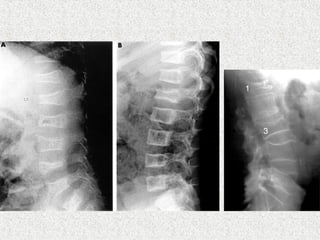

ļ‚ž Spinal deformity---Scoliosis/kyphosis

ļ‚ž Most common type of curve is thoracic

ļ‚ž Radiograph

ļ‚” Generalised osteopenia

ļ‚” Thinning of long bone

ļ‚” # in various stages of healing

ļ‚” Vertebral compression

ļ‚” Spinal deformity